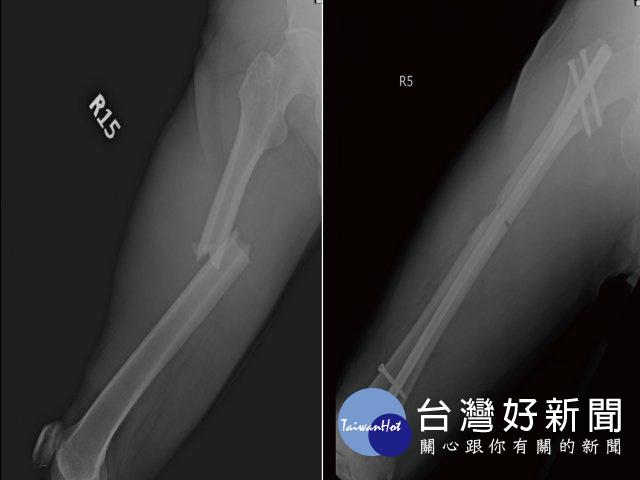

光田綜合醫院骨科王稚暉表示,王先生送抵急診檢查發現他三肋骨骨折、右腿股骨骨折、肝撕裂傷,合併有腹腔出血的狀況,院方當時緊急召集急診、一般外科、胸腔外科及骨科醫師共同治療下,手術縫合額頭傷口、股骨微創骨折復位固定,並給予輸液、輸血,病況始穩定下來。然考量飛機艙壓,王先生接受醫師建議在台灣多停留休養一周,讓身體有更多時間復原後再搭飛機返國。